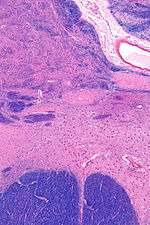

![]() Intermediate magnification micrograph of the nucleus basalis (of Meynert). LFB-HE stain. | |

NBM in relation to the globus pallidus and putamen - very low magnification.

NBM - very high magnification.